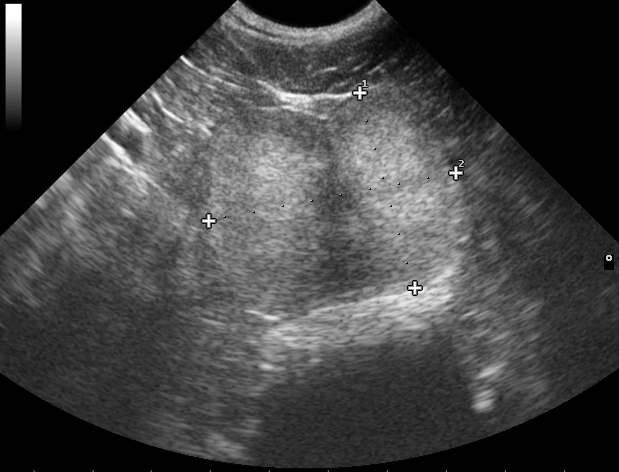

Močový aparát